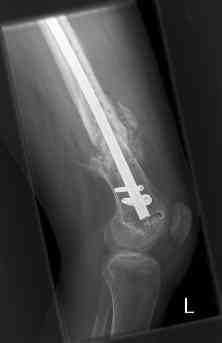

Aug 06

aug 06: blade plate + bone graft